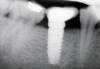

To avoid potential soft tissue collapse when the impression was captured, a custom impression abutment was created to support the soft tissue and properly communicate to the laboratory technician what had developed intraorally (Figure 10). This technique may be used with either open-tray or closed-tray impression abutments. The impression was taken and the custom healing abutment was reinserted intraorally while the laboratory constructed the restoration. The completed restoration was returned, the custom healing abutment was removed, and the implant restoration was inserted. The result was an emergence profile that mimicked a natural molar, enabling natural-looking esthetics (Figure 11). A radiograph demonstrated a smooth transition emanating from the implant platform to support an emergence profile that allowed soft-tissue maintenance and helped to eliminate potential food traps (Figure 12).

Fig 12. Radiograph of the final restoration demonstrating a natural emergence profile of the tooth that was replaced.

Figure 12